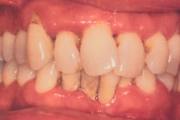

Vali sind huvitav pilt ja me näitame sellega seotud haigust ja sümptomeid